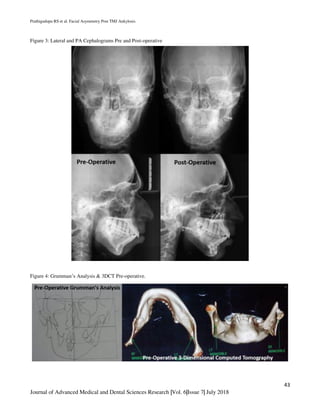

Figure 3: Lateral and PA Cephalograms Pre and Post-operative

Figure 4: Grumman’s Analysis & 3DCT Pre-operative.

leading to TMJ ankylosis. (Figure 3)Grumman’s analysis

and Three-dimensional computed tomography elicited

mandibular deviation on left side. (Figure 4). After